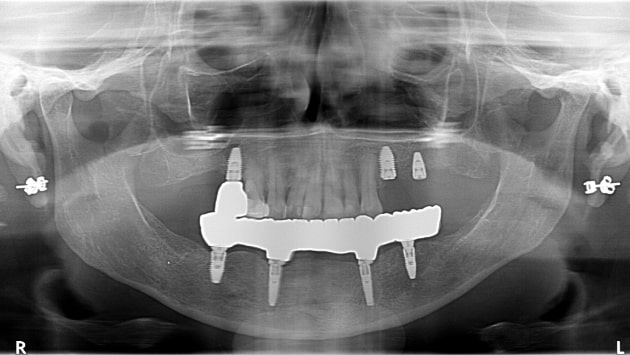

Snap On Dentures

Cost in Tijuana

Snap on dentures are the ideal choice for patients looking

for easy teeth maintenance and fewer visits to the dentist. As

they are easily removable for cleaning purposes, you can

take them off to clean them yourself.

This revolutionary way to attach your dentures onto

implants requires no messy pastes nor adhesives to be

retained. You will be able to eat, speak and smile freely and

comfortably!

A specialist will evaluate your dental status using X-rays, panoramic photos of your mouth, a 3D CBCT scan, and other techniques to provide you with the best treatment options and suggestions.